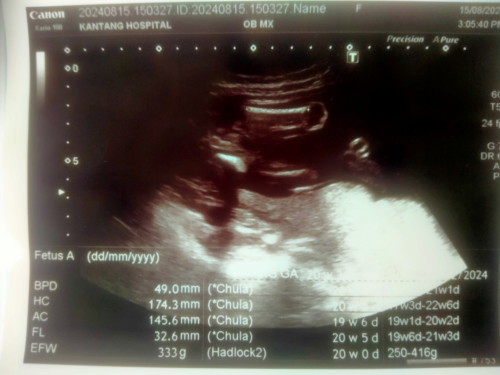

เเม่ช่วยดูเพศให้หน่อยนะค่ะ ซาวรพ.รัฐ หมอบอกไม่เห็นจู๋ เเต่ก้อไม่ได้บอกว่าผญ .100% แม่บ้านนี้ลุ้นมาก

ผู้หญิงคะ ไม่มีจู๋โผล่ตรงหว่างขา ถ้าผู้ชายจะ มีหน่อแบบนี้คะ อันนี้ตอน15w

มองไม่เห็นอะไรเลยค่ะ 🙏

21วีคเเล้วค่ะ